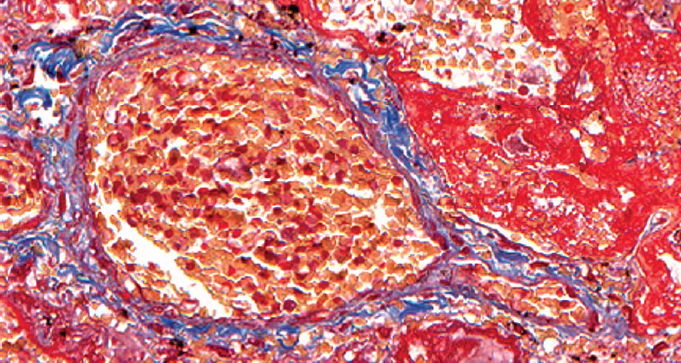

Children get sick less often than adults with a new coronavirus infection (in the Russian Federation, they account for 7.6% of registered cases of COVID-19), with less severe clinical symptoms, they require hospitalization less often, their disease is milder. The frequency of severe and extremely severe cases of COVID-19 in children does not exceed 1%. A clinical case of the course of COVID-19 in a child aged 2 years 4 months is presented. with acute lymphoblastic leukemia. A feature of the presented case is the development of an extremely severe new coronavirus infection in a child with secondary immunodeficiency caused by a long-term course of malignant, treatment-resistant of acute lymphoblastic leukemia. Slow, within 3 months, the development of the infectious process with long-term preservation of normal indicators of the function of the respiratory system led to the formation of viral-bacterial pneumonia with the development of respiratory distress syndrome. Despite the modern complex of therapeutic measures, severe comorbidity led to the development of DIC and multiple organ failure, which was the direct cause of the child’s death. A possible therapy strategy is discussed in a patient with severe comorbidity against the background of secondary immunodeficiency and long-term persistence of SARS-CoV-2 in the presence of IgG antibodies to SARS-CoV-2 in the blood. For the first time, data on morphological changes in the lungs with a long course of COVID-19 (more than 100 days) in a young child are presented.